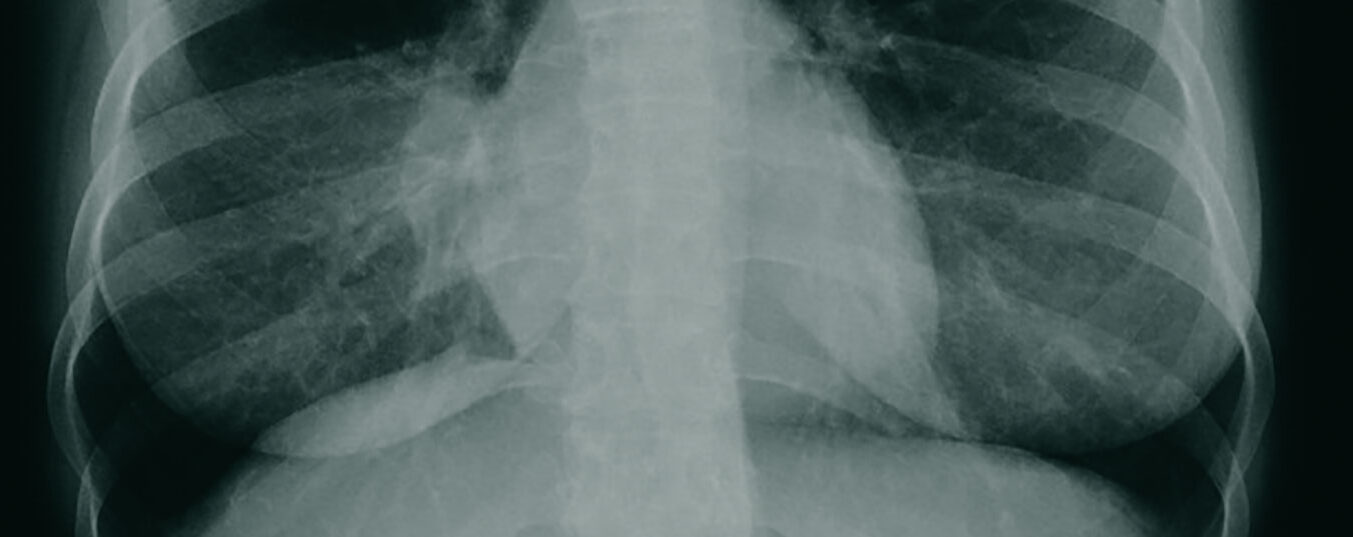

Woher kommt eigentlich… der Name «Pancoast-Tumor»?

Das Krankheitsbild des Pancoast-Tumors ist weit bekannt. Doch woher stammt eigentlich der etwas seltsam anmutende Name? Wir sind der Sache auf den Grund gegangen.